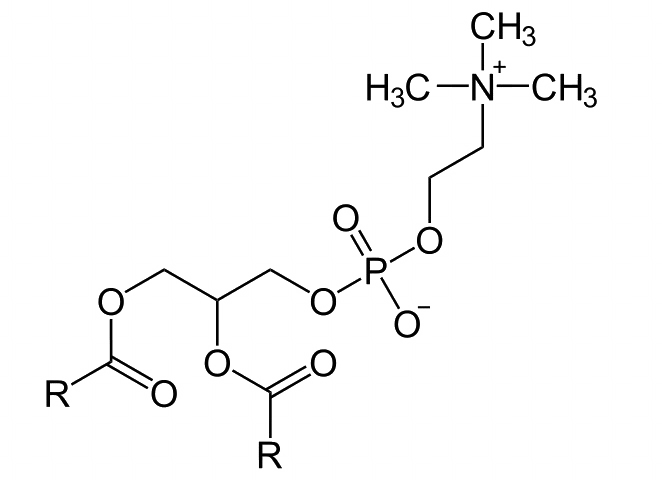

Soybean phospholipid

1-Palmitoyl-2-linoleoyl-sn-glycero-3-phosphocholine

Soybean lecithin

Soy lecithin

Phosphatidylcholine